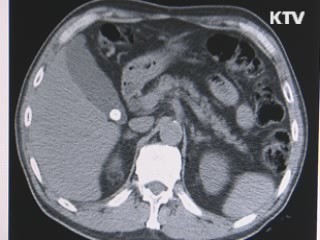

담석은 흔히 콜레스테롤 수치가 높은 중년층에서 많이 발생하는 것으로 알려져 있는데요.

몸짱이 되기 위해 과도한 다이어트를 하는 여성층에서도 발병률이 높은 것으로 나타났습니다.

담석증 환자와 그렇지 않은 사람의 초음파 사진을 비교해 봤습니다.

담낭 근처에서 하얗게 보이는 부분이 담석으로 환자는 우측 옆구리 쪽에서 쿡쿡 찌르는 통증을 느껴 병원을 찾았습니...